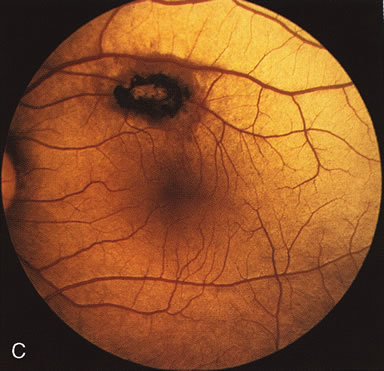

Fluorescein angiography highlights observable fundus findings. In patients with a golden reflex the FA is normal (Fig. 2E, F) or shows a mild transmission hyperfluorescence.7